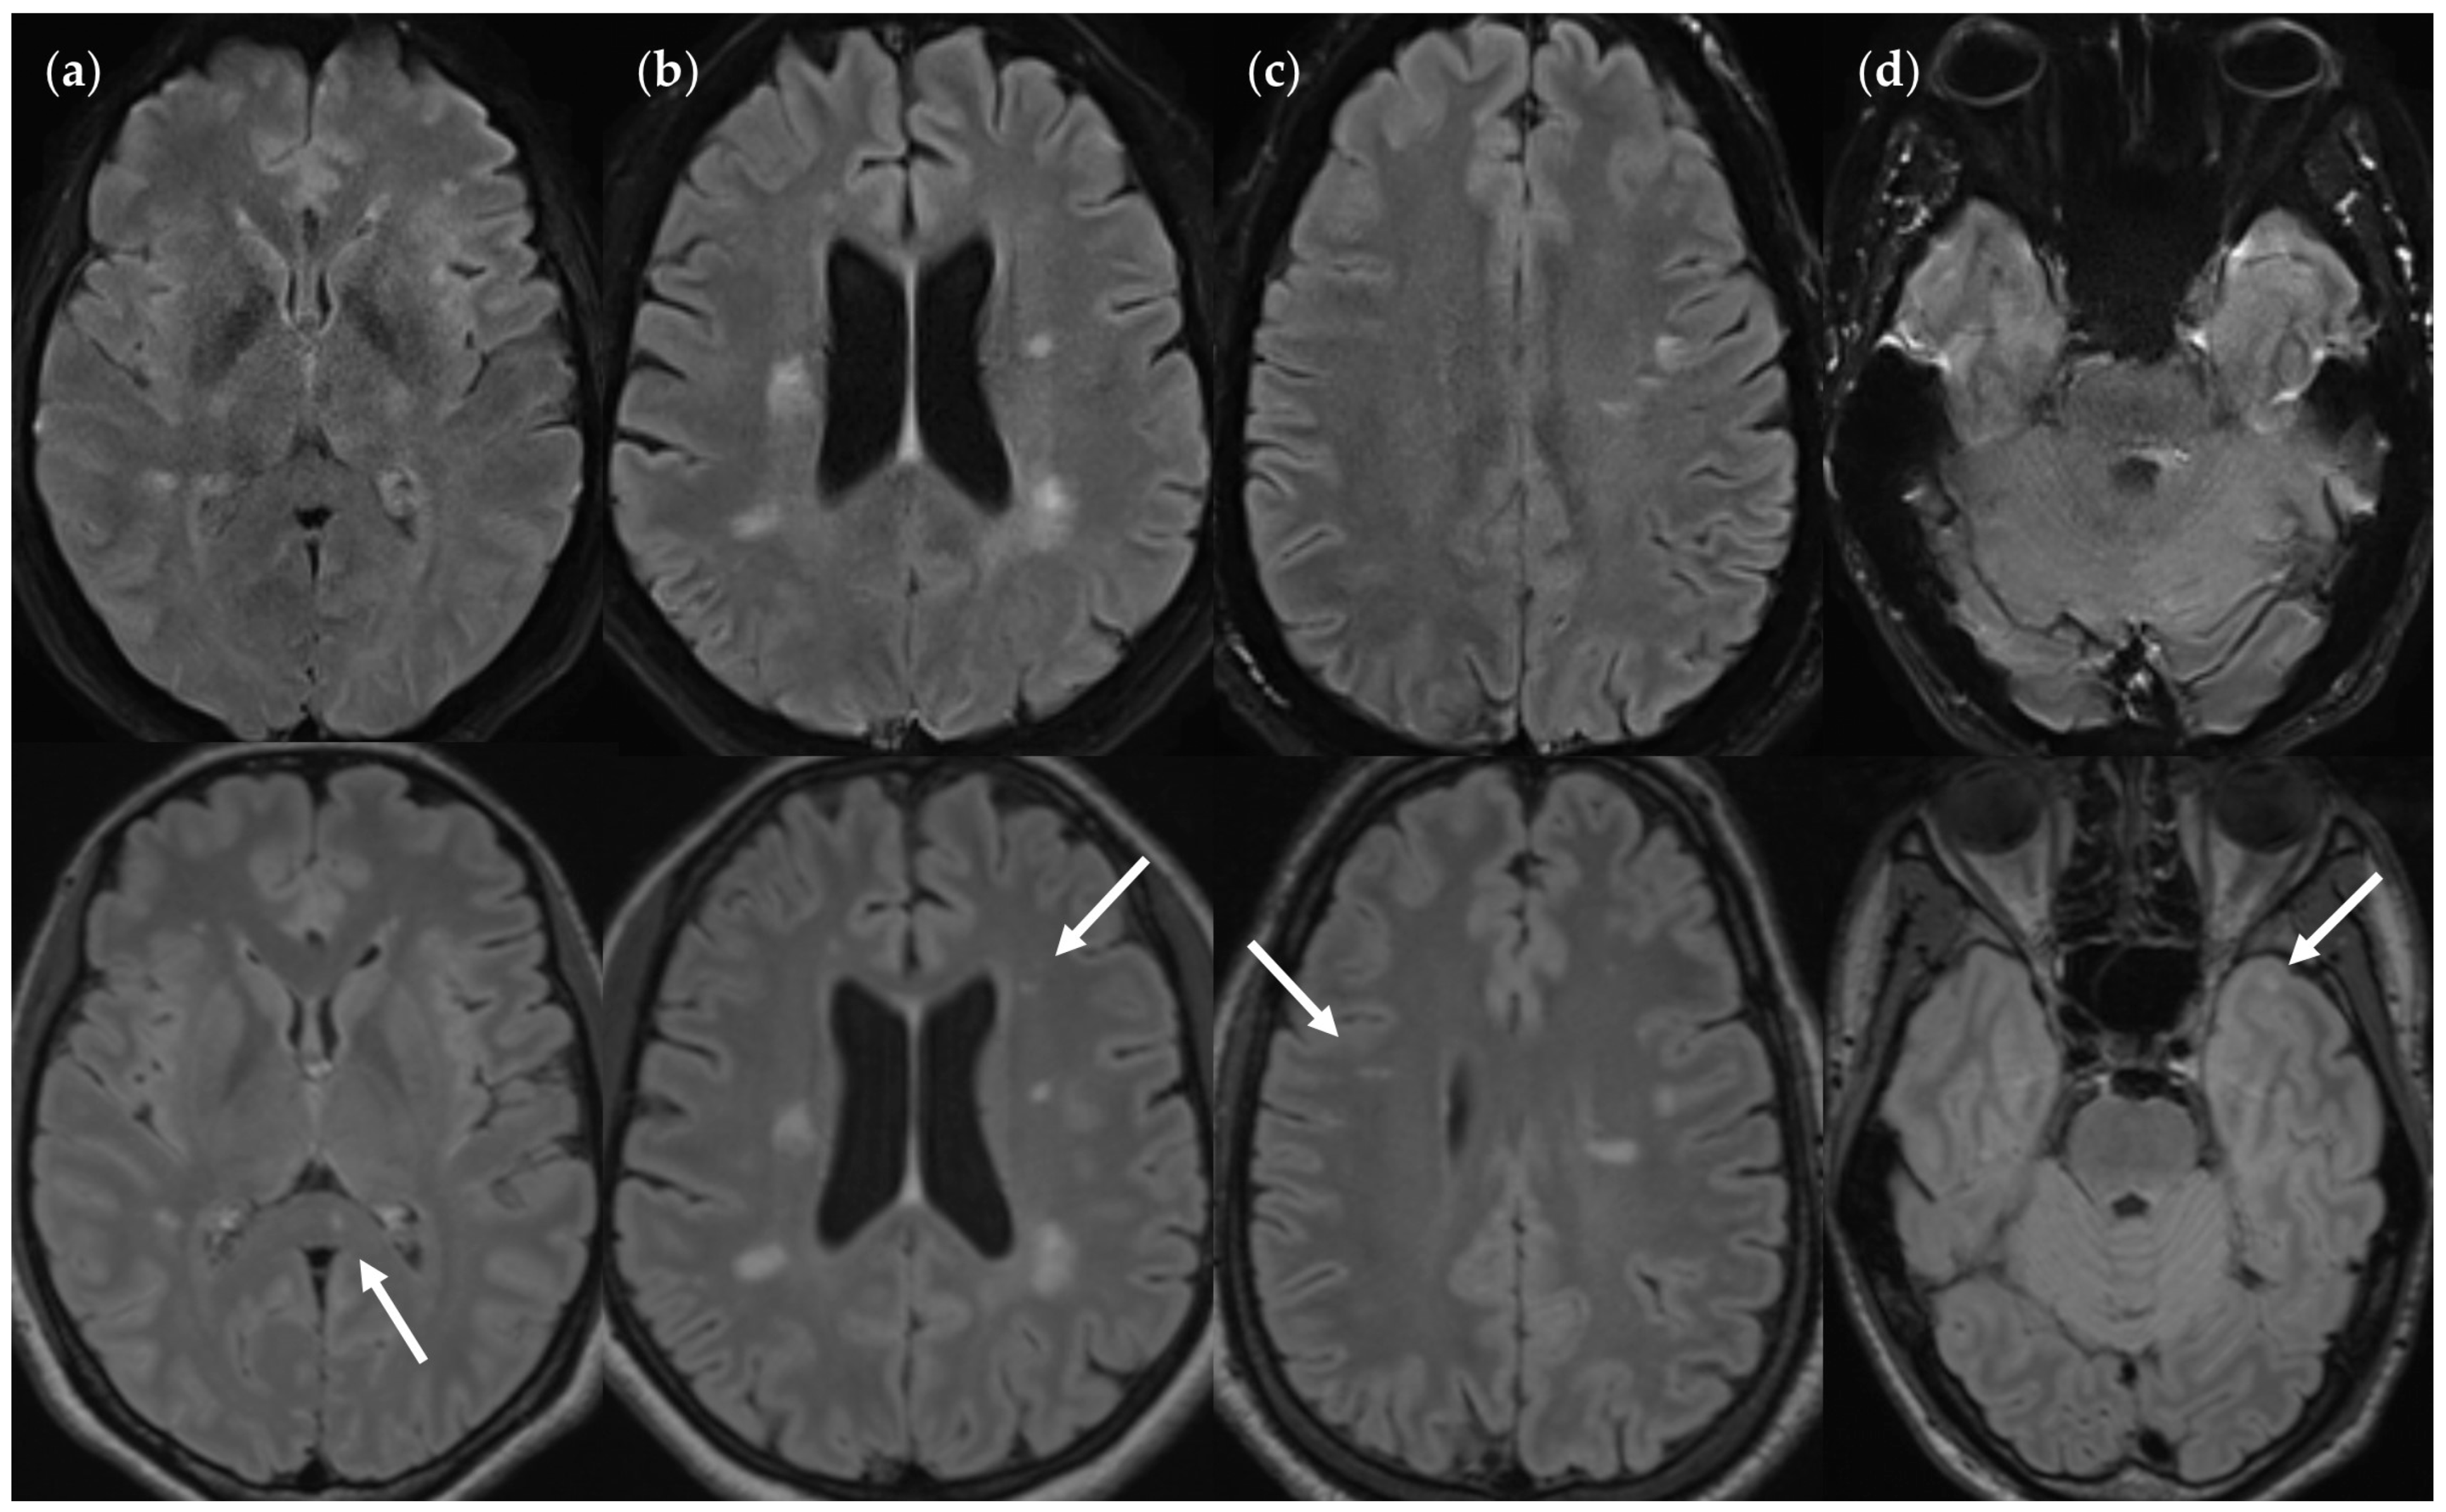

3.2.1. FLAIRUF Compared with FLAIR3Da

3.2.2. FLAIRUF Compared with FLAIRTSE

3.2.3. Dependence on Size and Location within FLAIRUF

4.3. Limitations of the FLAIRUF Images

4.4. Considerations on Ratings for Lesion Conspicuity in FLAIRUF

4.5. Outcomes Correlated with Technical Features